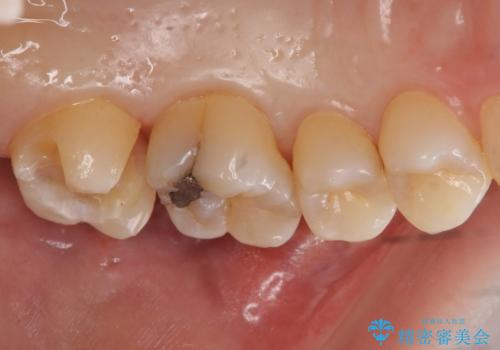

奥歯の虫歯 セラミックインレーによる治療

視診・レントゲン画像より虫歯の大きさを判断し、虫歯の除去後セラミックインレーにて修復することになりました。

セラミックインレー装着後は食べ物の詰まりも改善され、お掃除がしやすい環境になりとても満足していただけました。